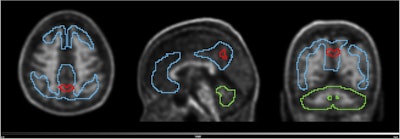

PET scans identify people at early risk for cognitive decline. Image from Guilherme Kolinger, MD, of Life Molecular Imaging in Germany, et al.

The second finalist for Best Radiology Image comes from a study reporting that amyloid PET scans in individuals with early signs of Alzheimer’s disease can identify those at higher risk of cognitive decline.

The study was conducted by scientists at Lantheus subsidiary Life Molecular Imaging, with the image demonstrating how quantitative analysis can reveal additional insights beyond standard visual assessment in amyloid PET.

“To identify the region highlighted in red, an amyloid-negative population (at baseline) with subjective cognitive decline was assessed with a voxel-based analysis using standardized uptake value ratios (SUVRs). Then, the baseline SUVR images of amyloid accumulators versus nonaccumulators were compared. Amyloid accumulation status was defined using the Centiloid method and with a five-year follow-up,” lead author Guilherme Kolinger, MD, explained to AuntMinnie.

The results showed that accumulators exhibited higher baseline SUVR in the red-marked region, which corresponds to part of the precuneus, a brain area known to play a role in early Alzheimer's disease. This region overlaps with the Centiloid target region (shown in blue), underscoring the potential of this approach to enhance preclinical Alzheimer's disease assessment, Kolinger added.